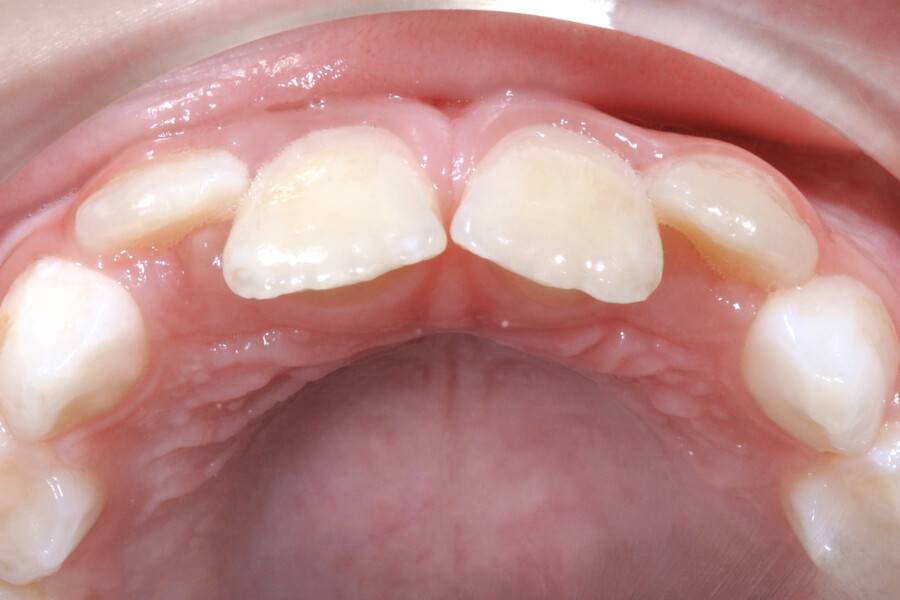

8 лет, девочка, жалобы на неправильный прикус и дефицит места зубам

Выполнено лечение с помощью LM-активатора на ночь